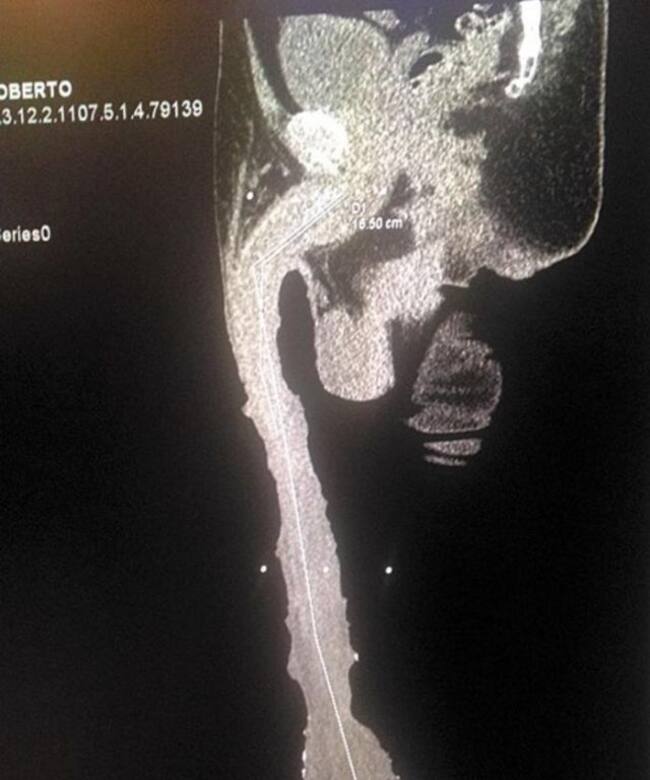

El hombre con el aparato reproductor más grande con un tamaño de 48.2 cm

Los médicos determinaron que 32 centímetros son de piel que creció de manera extraordinaria; falta determinar si este crecimiento es por causas artificiales y los riesgos que implica.